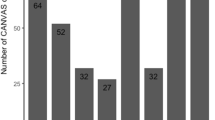

While clinical descriptions of CANVAS are uncommon, it is possible that its prevalence could exceed initial expectations. Quite a few population-based assessments reported elevated carrier frequencies of the pathogenic (AAGGG)n motif coupled with dwindled biallelic rates (Fig. 1). The majority of confirmed patients so far, both clinically and genetically, have come from communities in Europe [10, 11]. At the outset, 92% of instances having complete CANVAS, 54% of cases with cerebellar ataxia and sensory neuropathy, and 22% with late-onset ataxias showed biallelic pathological RFC1 expansions [11]. Contemporary studies have independently revealed the presence of the pathological biallelic RFC1 expansion in ataxia cohorts; however, the reports indicated higher prevalence in full-blown CANVAS cases and lower prevalence in cases involving late-onset ataxia and incomplete CANVAS. In line with diverse studies, individuals from northern European origin have shown up with carrier frequency of RFC1 heterozygous (AAGGG)exp [1] to range from 0.7 to 4%, with an approximate prevalence of RFC1-related diseases of 1/20,000, i.e. 1:625. The Chinese population has also shown an analogous allele frequency of 2.24%. Whereas, 1.8% of the Japanese population (1/55) have shown heterozygous RFC1 (AAGGG)exp [12]. The occurrence of harmful RFC1 gene expansions (AAGGG)n has been demonstrated to differ notably among various groups of individuals with late-onset ataxia. This ranges from 1.1% in a study involving Canadian and Brazilian participants to as high as 28.9% in a British cohort. In other studies, the prevalence was found to be 3.2% in a North American group, 6.5% in a Greek cohort, 5.2–10.8% in Japanese cohorts, 14% in a Turkish cohort, 14.5% in an Italian cohort, 15% in a French cohort and around 20.2% in a German cohort (Table 1) [13,14,15]. Variations in the criteria used for participant selection can be assumed to contribute significantly to the range of prevalence rates observed across numerous cohort studies focused on late-onset ataxias. Another potential factor could be the presence of population-specific variables that may exert an influence on these figures. The AAGGG expansion manifests at a comparable allele frequency in Asian populations, though the impact of RFC1 on disease within these populations is significantly less pronounced in comparison to European populations. Cortese et al. reported the non-pathogenic allele frequency to be 13% for (AAAAG)exp, 7.9% for (AAAGG)exp and 2.1% for (AAGAG)exp [11]. The allelic distribution for biallelic (AAGGG)exp in association with CANVAS has been reported to be around 0.7–6.8% [16]. These collective findings emphasize that late-onset ataxia patients, especially those with accompanying sensory neuropathy, frequently exhibit genetically confirmed CANVAS. Hence, it is crucial to conduct screenings for biallelic RFC1 expansions in individuals presenting with complete CANVAS, partial CANVAS, or unexplained sensory ataxia. This proactive approach can ensure comprehensive care for these patients.

In 2011, Szmulewicz et al. introduced the acronym “CANVAS” to describe a condition associated with the late emergence of symptoms including cerebellar ataxia, sensory neuropathy and vestibular areflexia [17]. Concurrently, these patients exhibited cerebellar atrophy and persistent chronic cough. The chronological course of CANVAS demonstrates an escalating profile and amplification of its overall symptoms or characteristics (Fig. 2). Migliaccio et al. initially documented four cases featuring gradual sporadic cerebellar ataxia, coupled with a decline in vestibulo-ocular reflex [18]. In a study involving 80 individuals experiencing late-onset cerebellar ataxia, the findings revealed that 33% of the patients had an expression of multiple system atrophy (MSA), another 33% were associated with acquired causes, and the remaining cases were diagnosed as idiopathic late-onset cerebellar ataxia (ILOCA), linked to CANVAS [19]. Derived from an examination of 150 cases, where 22 familial cases were diagnosed with CANVAS alongside ILOCA, the study emphasizes that CANVAS contributes to 20% of the cases involving ILOCA [11]. But in the most current scenario, the central characteristics of the clinically possible CANVAS have evolved. There have been significant efforts to understand the clinical aspects of the disease and it has been observed that the emergence of the last element in the diagnostic triad may extend beyond a decade. Therefore, a patient initially presenting with cerebellar ataxia and bilateral vestibulopathy (CABV), or any other combination of two of the three primary features of CANVAS, should undergo initial assessments. Consequently, it is recommended that these individuals undergo regular reassessment to ascertain whether they have begun to develop a progressive form of CANVAS [20]. According to Cortese et al. the disease turns to transition gradually from initial occurrence of sensory neuron deficits to later manifestations of vestibular and cerebellar dysfunctions [4].